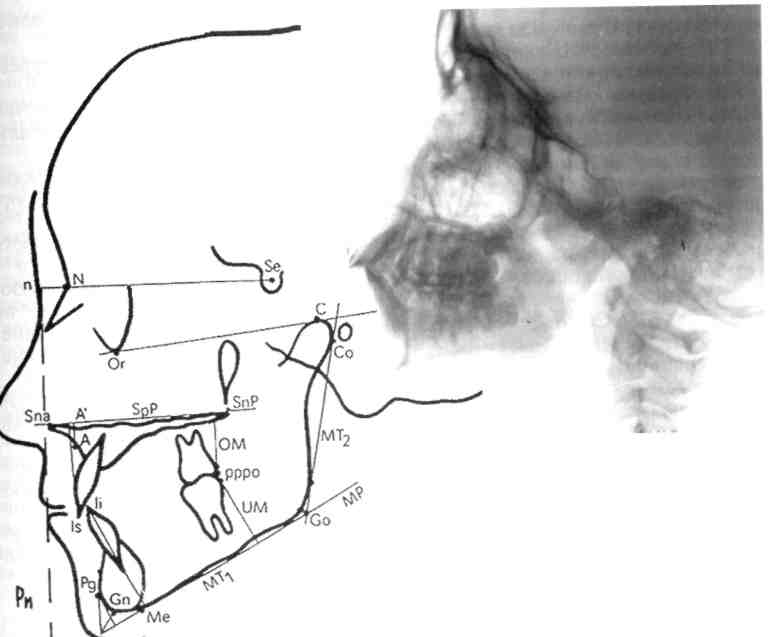

Рис. 13.28.Телерентгенограмма го­ловы, выполненная в боковой про­екции.

Телерентгенография. Этот метод рентгенологического исследования применяют для изучения строения Хевого скелета, его роста, уточ­нения диагноза и прогноза орто-лонтического лечения, а также для выявления изменений, происходя­щих в процессе лечения. Телерент­генографию проводят в боковой и прямой проекциях с расстояния 1 5 м Голову обследуемого фикси­руют с помощью цефалостата раз­личных конструкций, применение которых обеспечивает получение идентичных снимков (рис. 13.28).

челюстной системы в трансверсаль-ном направлении, в боковой проек­ции — в сагиттальном и трансвер-сальном направлениях. На ТРГ видны кости лицевого и мозгового черепа и контуры мягких тканей, что дает возможность изучить их взаимоотношения (рис. 13.29).

Для расшифровки ТРГ снимок помещают на экран негатоскопа, к

нему прикрепляют кальку, на кото­рую переносят изображение.

ТРГ по методу Шварца позволя­ет наиболее полно изучить размер и положение челюстных костей. Пользуясь этим методом, можно провести краниометрические, гна-тометрические и профилометриче-ские измерения. С помощью кра­ниометрии определяют: 1) распо­ложение челюстей в сагиттальном и вертикальном направлениях по отношению к плоскости передней части основания черепа; 2) распо­ложение ВНЧС по отношению к плоскости передней части основа­ния черепа; 3) длину передней час­ти основания черепной ямки.

Для анализа ТРГ используют сле­дующие точки плоскости:

\ — субспинальную точку Downs, наиболее глубокую на перед­нем контуре апикального ба­зиса верхней челюсти;

3 — супраментальную точку

Downs, наиболее дистально расположенную на переднем

pg — самую переднюю точку под­бородочного выступа;

р^§е _- плоскость переднего отдела основания черепа (ее прово­дят через точки N и Se);

gpP _ плоскость основания верх­ней челюсти (проходит через точки Sna и Snp);

рп — носовая вертикаль, которую проводят перпендикулярно к плоскости NSe через кож­ную точку п;

MP — плоскость основания ниж­ней челюсти.

На ТРГ отделяют краниальную часть черепа от гнатической плос­кости верхней челюсти (SpP).

Варианты расположения челюстей определяют по лицевому, инклина-ционному углу и углу горизонтали:

1) лицевой угол. F образуется при пересечении линий N—Se и N—А (внутренний нижний угол). Его ве­личина характеризует расположе­ние верхней челюсти по отноше­нию к основанию черепа в сагитта­льном направлении. Угол меньше нормы характерен для ретрогнатии, больше нормы — для прогнатии; если он находится в пределах нор­мы, говорят о нормогнатии;

2) угол горизонтали Н образуется при пересечении линии Н (гори­зонтальная линия) и Рп (внутрен­ний верхний угол) и определяет по­ложение суставной головки нижней челюсти по отношению к основа­нию черепа, что влияет на форму профиля лица;

3) инклинационный угол J образу­ется при пересечении линий Рп и SpP (внутренний верхний угол). Если угол J больше средней вели­чины, то челюсти наклонены впе­ред, что Шварц назвал антеинкли-нацией. Если угол меньше средней величины, то челюсти отклонены назад. Такое положение челюстей называется ретроинклинацией.